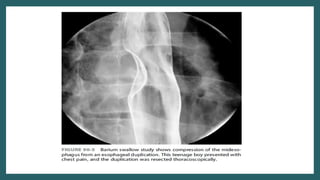

Thoracic and Thoracoabdominal

duplication

• 20% of alimentary tract duplications -thorax or are

thoracoabdominal.

• Location-Lower half of posterior mediastinum

• Most fall in neuroenteric cyst group

• Frequently associated with vertebral anomalies

• Asympyomatic +/- Respiratory distress

• CT scan-Investigation of choice

• Treatment-Primrary excision